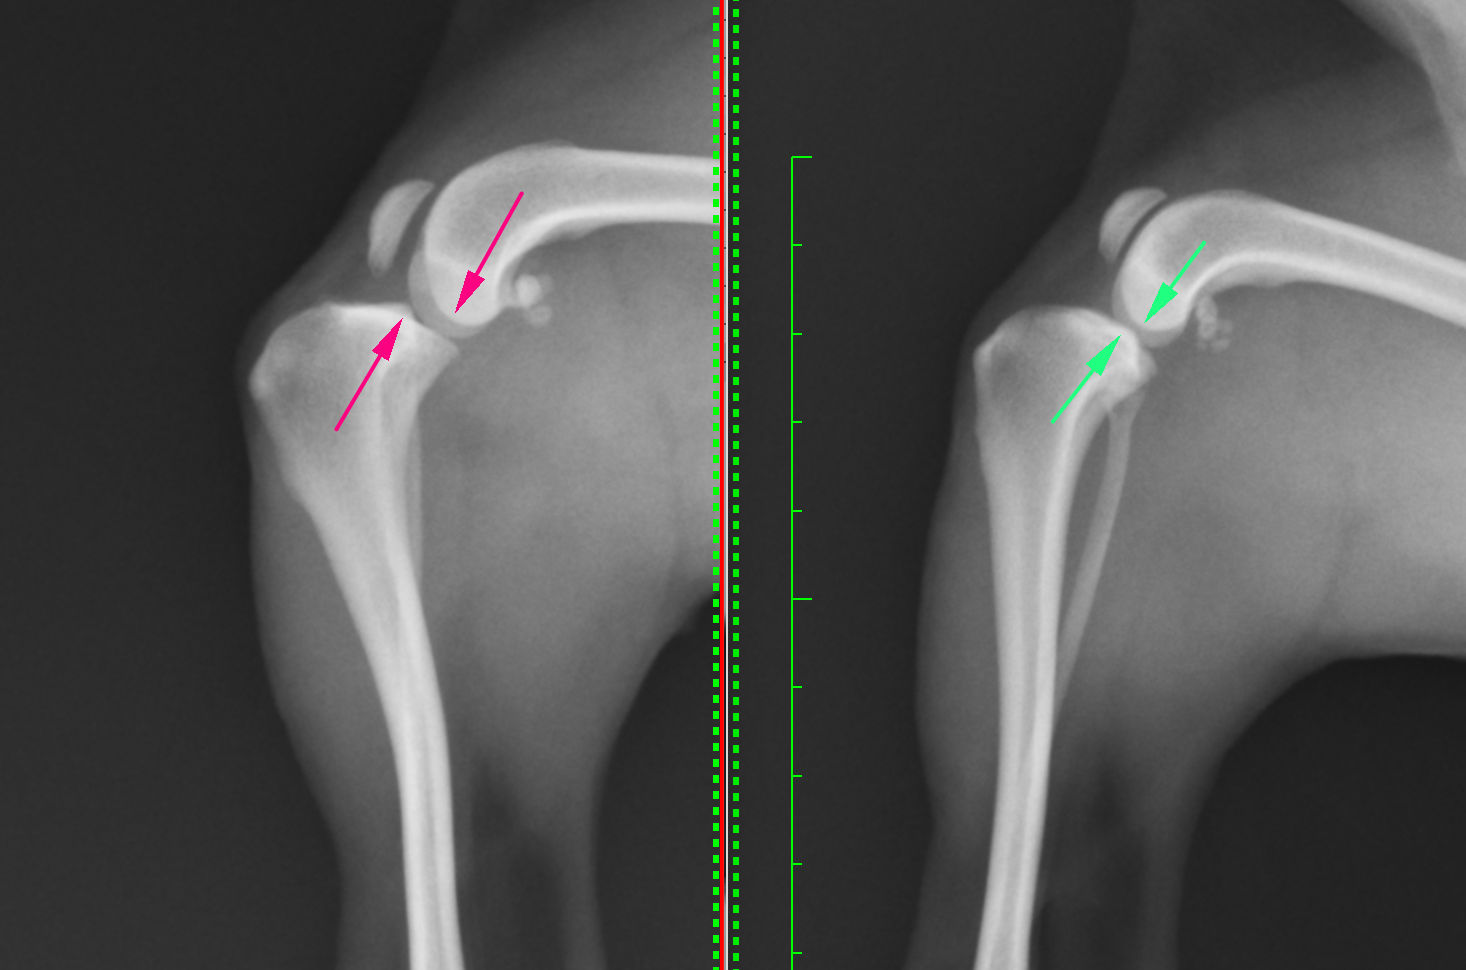

右が通常の膝のレントゲンです。緑矢印の部分(脛骨高平部と大腿骨遠位外顆内顆)が一致しているのがわかると思います。左が前十字靭帯断裂の膝のレントゲンです。矢印の部分がずれているのがわかります。脛骨が前方変位しています(CrTTといいます)。